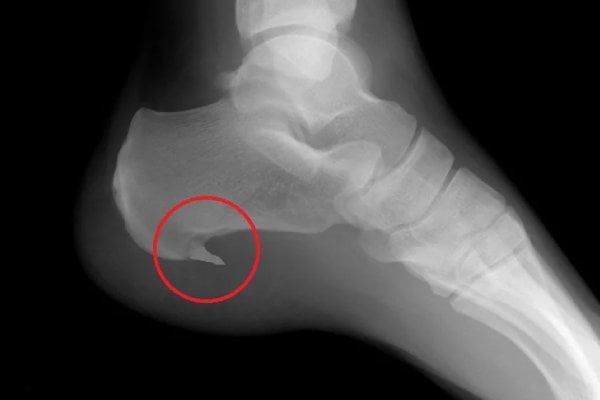

Hielspoor (plantaire fasciitis) is een ontsteking van de peesplaat onder uw voet. Dit is een dikke band van bindweefsel die van uw hiel naar uw tenen loopt en uw voetboog ondersteunt.

Het botuitsteeksel, de “spoor”, veroorzaakt zelden pijn. De echte boosdoener is de ontstoken aanhechting van de peesplaat aan het hielbeen.

Typische klachten: pijn onder de hiel bij de eerste stappen ’s ochtends, verbetering tijdens bewegen maar terugkeer na rust.